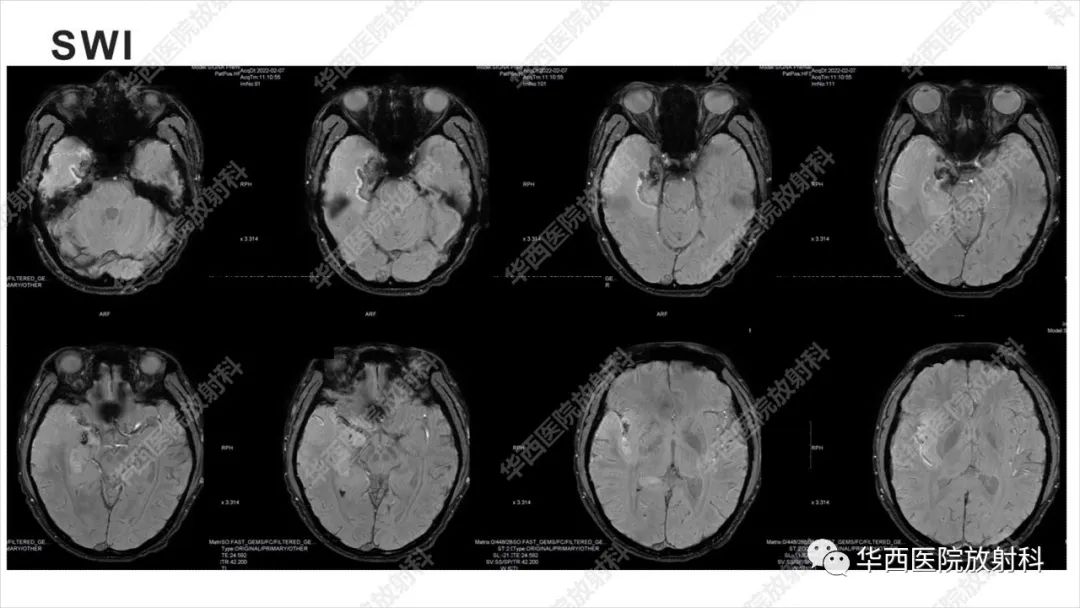

【病例】出血坏死性病毒脑膜脑炎1例CT及MR影像学表现和鉴别诊断-2